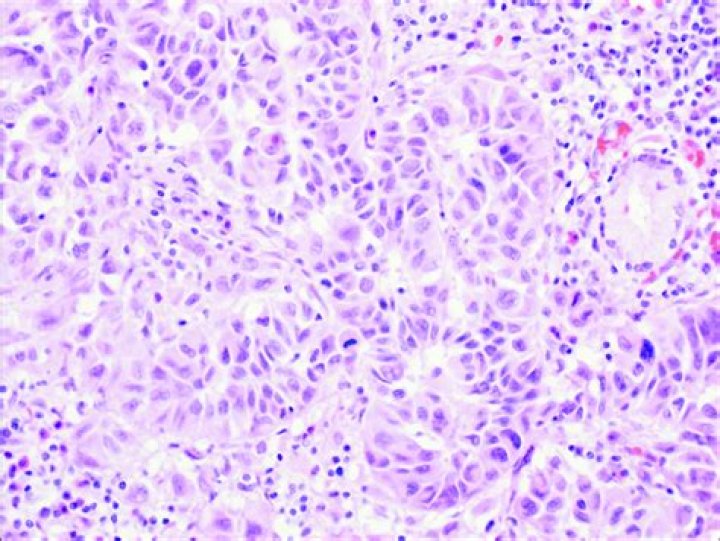

Microscopically, small cell carcinoma is composed of sheets of cells that have small- to intermediate-sized dark, hyperchromatic nuclei with indistinct nucleoli and scant cytoplasm. The nuclei often form to and indent one another (the so-called nuclear molding) (Figure 30).

The tumors usually present as a nodule on the head or neck. The nuclei of the giant tumor cells are irregularly shaped, hyperchromatic, and 2 to 10 times larger than the nuclei of the surrounding cancer cells. Atypical mitoses may be present.

Enlarged nuclei with hyperchromatic, irregular clumps of chromatin separated with blurred, pale, or clear areas (parachromatin clearing) may occur. These findings may mimic the nuclear changes of malignancy.